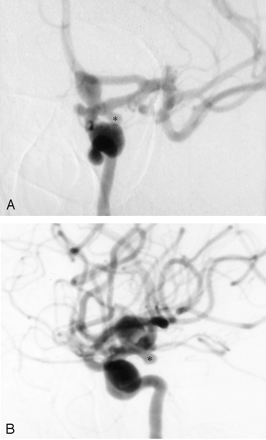

A 45-year-old woman with chronic headaches presented after a fall. She had a long history of smoking with no other relevant medical history. She had no known familial history of aneurysms. Her CT and MR imaging studies of the head suggested multiple cerebral aneurysms. Diagnostic cerebral angiography performed at an outside hospital revealed multiple bilateral internal carotid artery aneurysms. Five aneurysms were present on the left internal carotid artery: a 12-mm cavernous, a 9-mm ophthalmic, a 3-mm ophthalmic, a 4-mm posterior communicating, and a 2-mm anterior choroidal artery aneurysm (Fig 1A and B). Three aneurysms were found on the right internal carotid artery carotid: a 3-mm cavernous segment, a 7-mm carotid cave, and a 2-mm anterior choroidal aneurysm. No aneurysms were found in the posterior circulation.

Angiograms from the case of a 45-year-old woman with chronic headaches who presented after experiencing a fall. Five aneurysms were present on the left internal carotid artery.

A, Anteroposterior view angiogram of the left internal carotid artery shows multiple aneurysms. These include a large cavernous carotid aneurysm, a small ophthalmic segment aneurysm, a large ophthalmic segment aneurysm, and a posterior communicating artery aneurysm (asterisk). A tiny anterior choroidal aneurysm is also present.

B, Lateral view angiogram of the left internal carotid artery. Astserisk indicates posterior communicating artery aneurysm.